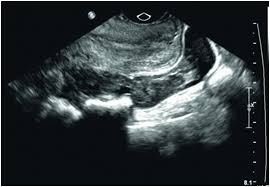

Ultrasound Video Showing Missed Abortion With Fluid In Cul De Sac.